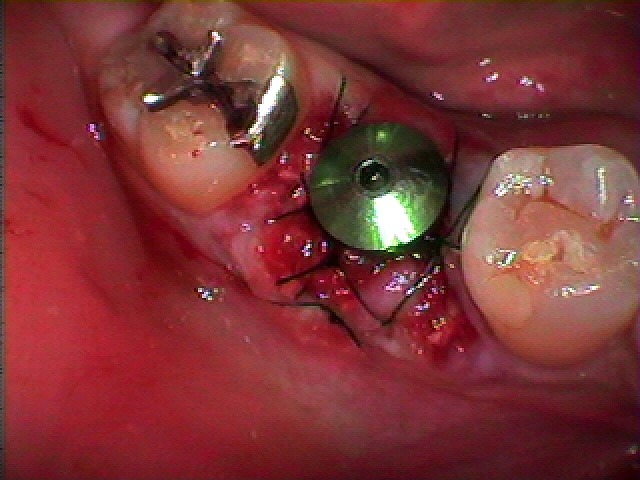

インプラントを埋入していきます

骨補填材を転入していきました

縫合して終了となります